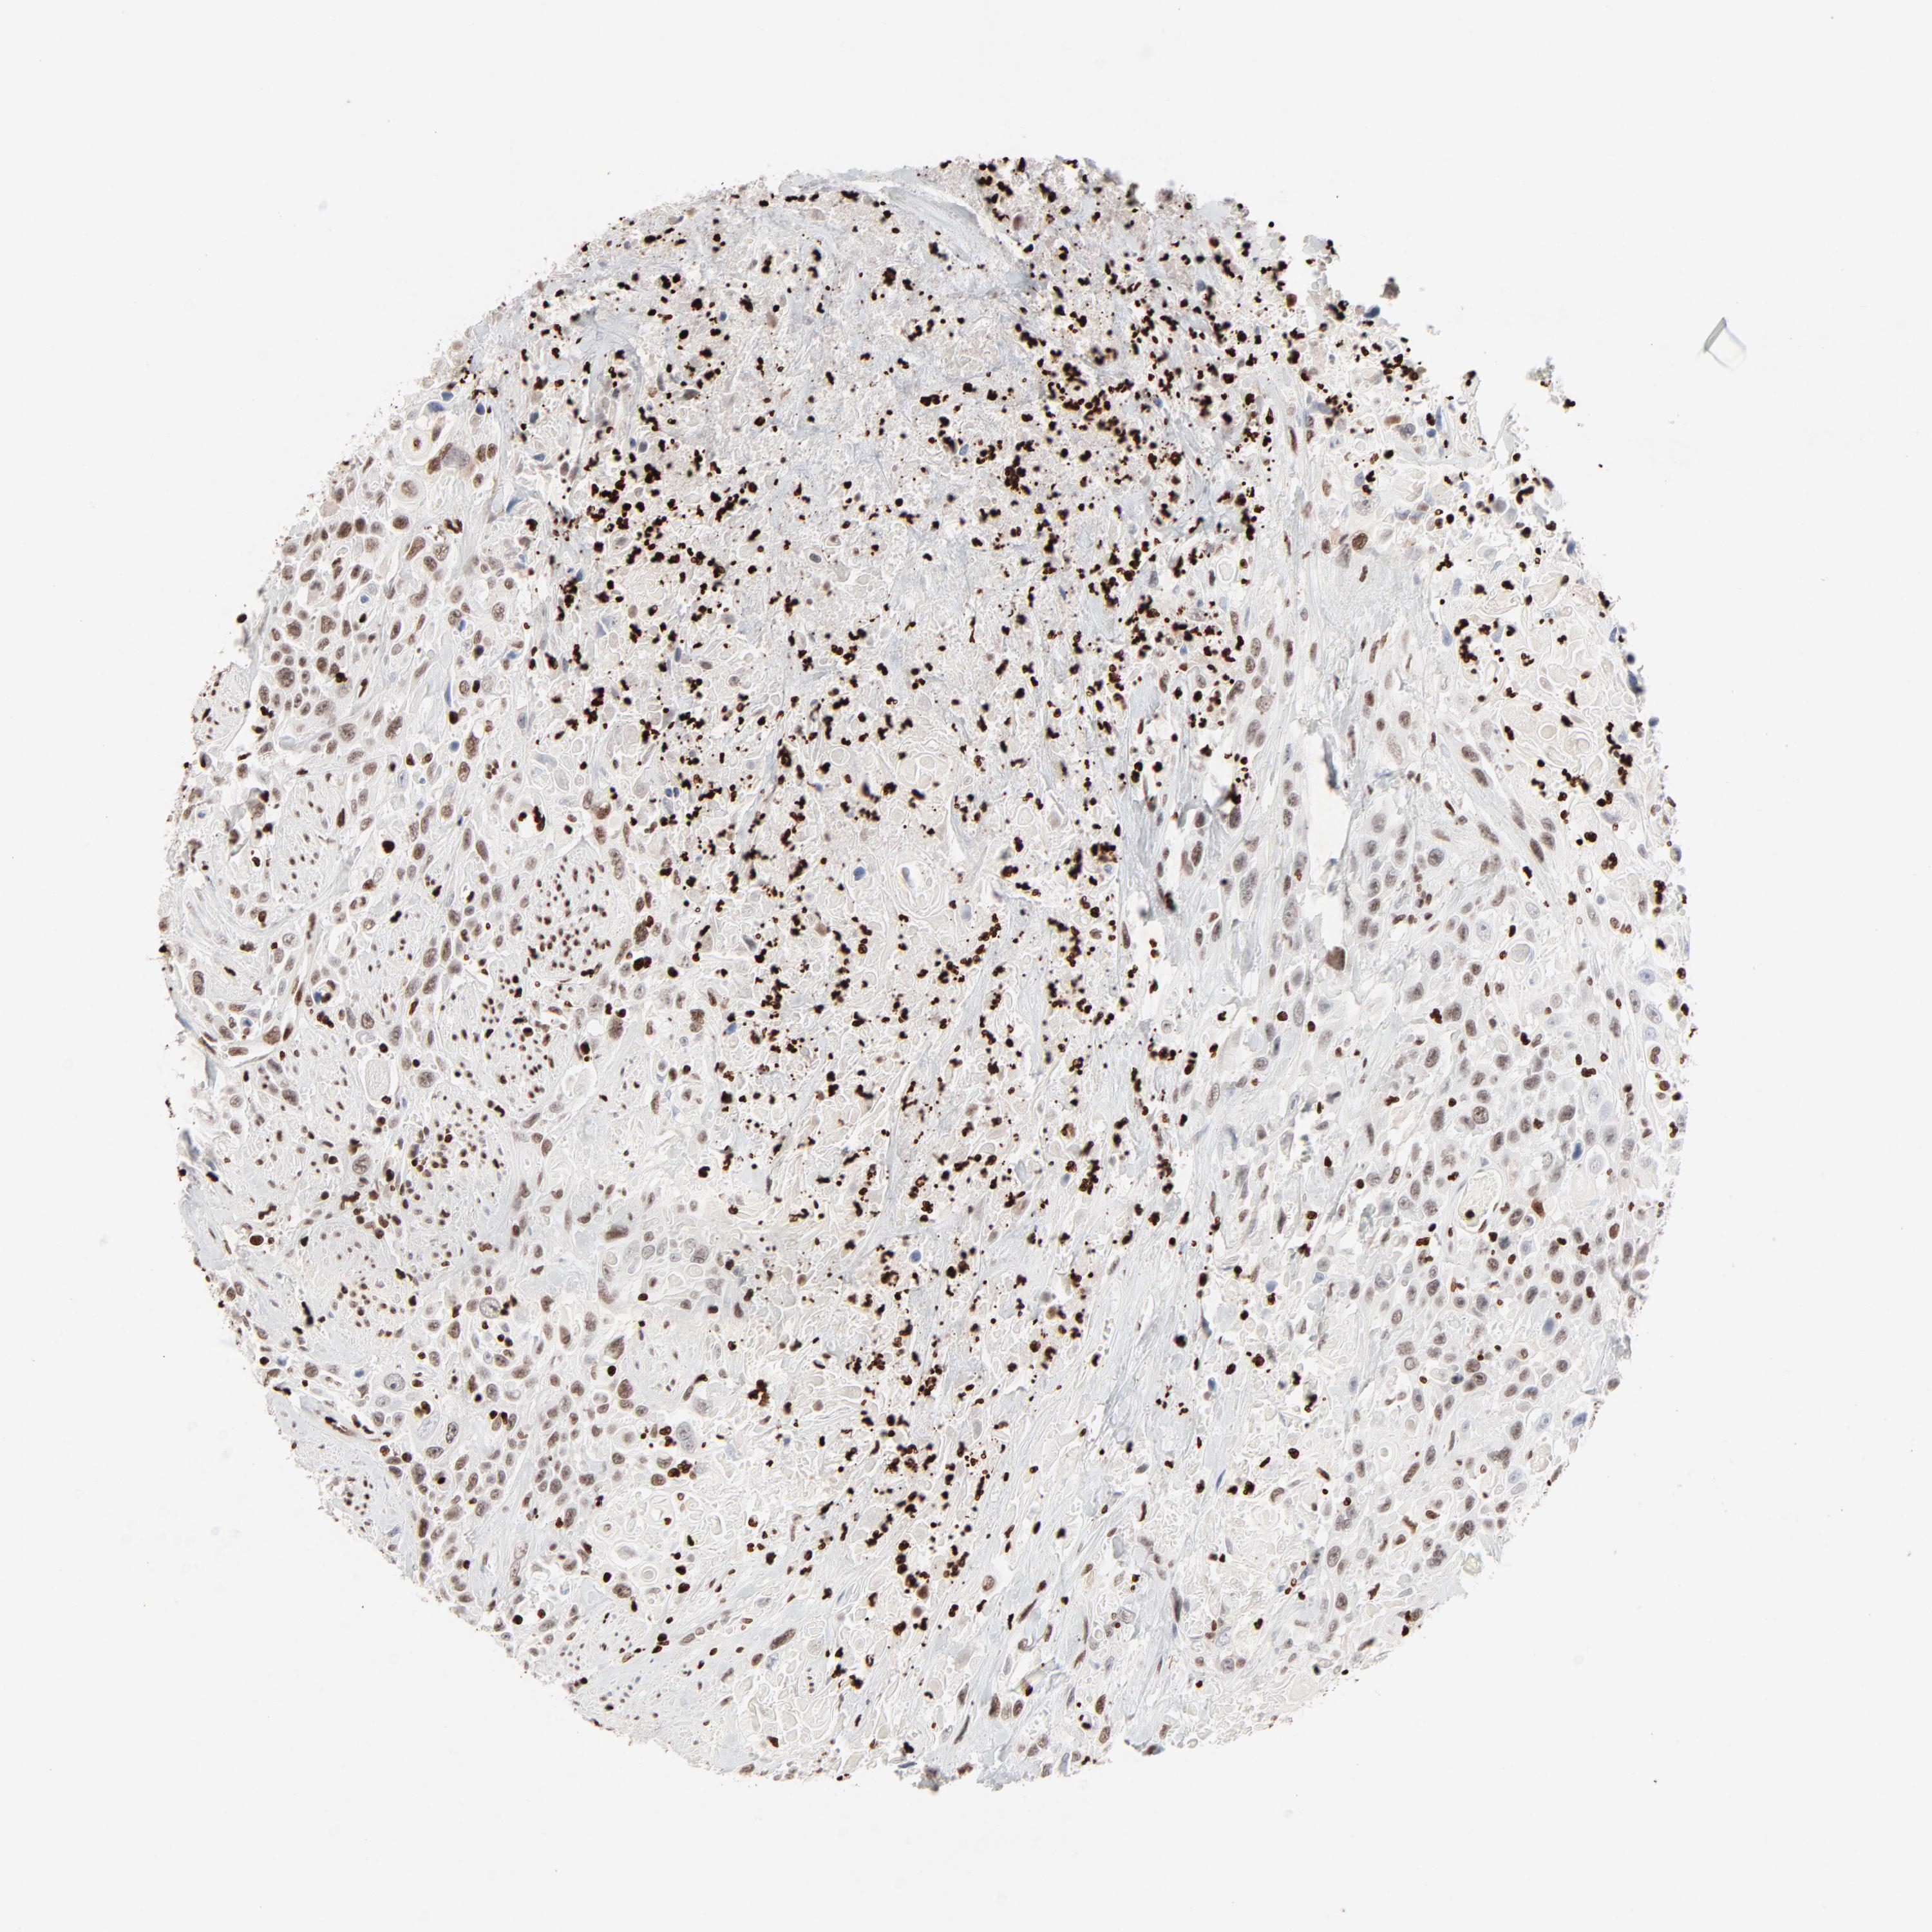

UROTHELIAL CANCER - Protein expressioni

A mouse-over function shows sample information and annotation data. Click on an image to view it in a full screen mode. Samples can be filtered based on level of antibody staining by selecting one or several of the following categories: high, medium, low and not detected. The assay and annotation is described here.

Note that samples used for immunohistochemistry by the Human Protein Atlas do not correspond to samples in the TCGA dataset.

Antibody stainingi

Antibody staining in the annotated cell types in the current human tissue is reported as not detected, low, medium, or high, based on conventional immunohistochemistry profiling in selected tissues. This score is based on the combination of the staining intensity and fraction of stained cells.

Each image is clickable and will lead to virtual microscopy that enables deeper exploration of all samples and also displays staining intensity scores, fraction scores and subcellular localization as well as patient and tissue information for each sample.

Antibody HPA003506

Antibody CAB005873

Staining

High

Medium

Low

Not detected

Intensity

Strong

Moderate

Weak

Negative

Quantity

>75%

75%-25%

<25%

None

Location

Nuclear

Cytoplasmic/membranous

Cytoplasmic/membranous,nuclear

Urothelial carcinoma, High grade

Urothelial carcinoma, Low grade